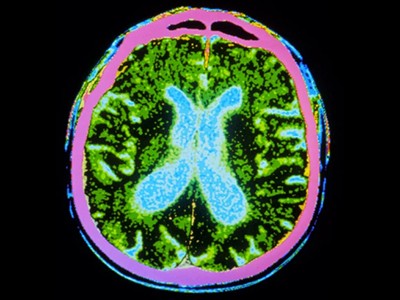

帕金森病是由于大腦中釋放多巴胺(多巴胺能)神經(jīng)元逐漸喪失所致。Sawamoto 等人1和 Tabar 等人2進行了一項基于干細胞治療的臨床試驗。兩個團隊都使用了臨床級多能干細胞來補充多巴胺能神經(jīng)元,這種細胞可以無限分裂并分化為任何細胞類型。Sawamoto等人使用了源自健康成年捐贈者細胞的誘導多能干細胞系,而Tabar等人使用了源自早期胚胎的人類胚胎干細胞系。干細胞經(jīng)過培養(yǎng),形成多巴胺能神經(jīng)元祖細胞。這些細胞被移植到稱為殼核的大腦區(qū)域,殼核與尾狀核一起形成紋狀體。紋狀體與黑質(zhì)相連,而黑質(zhì)是多巴胺能神經(jīng)元損失最為嚴重的部位。早期(I/II期)臨床試驗主要證實了該療法的安全性,同時也表明其在改善癥狀方面具有一定有效性。